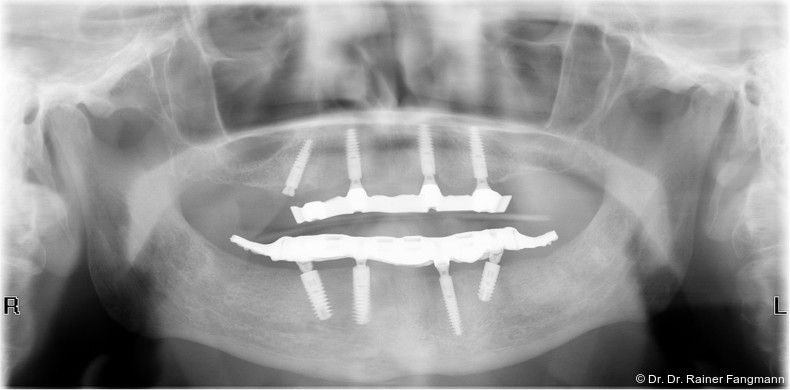

Die Fragestellung zur Implantatanzahl im Oberkiefer oder Unterkiefer ist oft sehr patienten- und behandlerspezifisch zu betrach-ten. Für Kostenträger ist die Frage oft von übergeordneter Relevanz. Für den Praktiker stellt sich die Frage nach der Umsetzbarkeit. Zudem sind auch das Knochenangebot und dessen Qualität für die Anzahl der Implantate und auch der Implantattypus maßgebend. Folgender Beitrag zeigt ein Fallbeispiel mit drei Implantaten, sechs Jahre in situ.

Ein immer viel diskutiertes Thema ist die Implantatanzahl beim All-on-X-Konzept. Diese ist von vielen Faktoren abhängig. Zu nennen sind der Implantattyp, der Implantatdurchmesser und die Implantatinnengeometrie. Im Weiteren sind die Knochenqualität und -quantität zu betrachten. Auch spielt die Gegenbezahnung zum All-on-X-Kiefer eine entscheidende Rolle, sodass hier keine einheitliche Linie für den Oberkiefer erkennbar ist. Es gelten in der Regel vier bis sechs Implantate als ausreichend. Im Unterkiefer sind es in der Regel vier. Wie dargestellt, reichen bei diesem Implantatsystem auch drei Implantate aus.